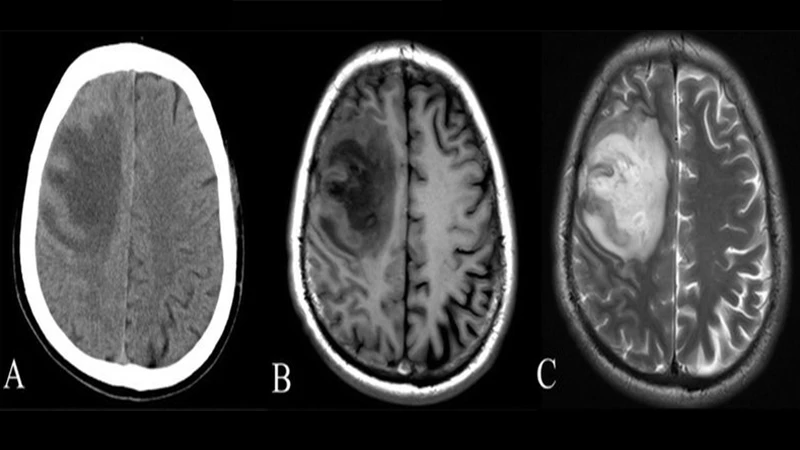

MRI excels at imaging soft tissues. It provides unparalleled detail of the brain, spinal cord, ligaments, tendons, and muscles. This makes it the superior choice for diagnosing conditions like ligament tears, tumors in soft tissue, and neurological diseases.

Side-by-side comparison of a CT scan and an MRI of a head, showing CT's detail in bone and MRI's superior detail in brain tissue.